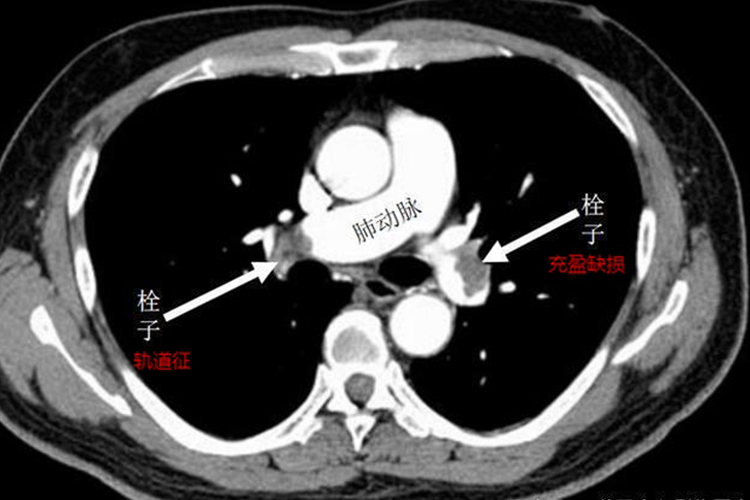

CT具有无创、扫描速度快、图像清晰、较经济的特点,可直观判断肺动脉栓塞的程度和形态,以及累及的部位及范围。肺栓塞直接征象为肺动脉内低密度充盈缺损,部分或完全包围在不透光的血流之内的“轨道征”,或者呈完全充盈缺损,远端血管不显影;间接征象包括肺野楔形条带状的高密度区或盘状肺不张,中心肺动脉扩张及远端血管分布减少或消失等。